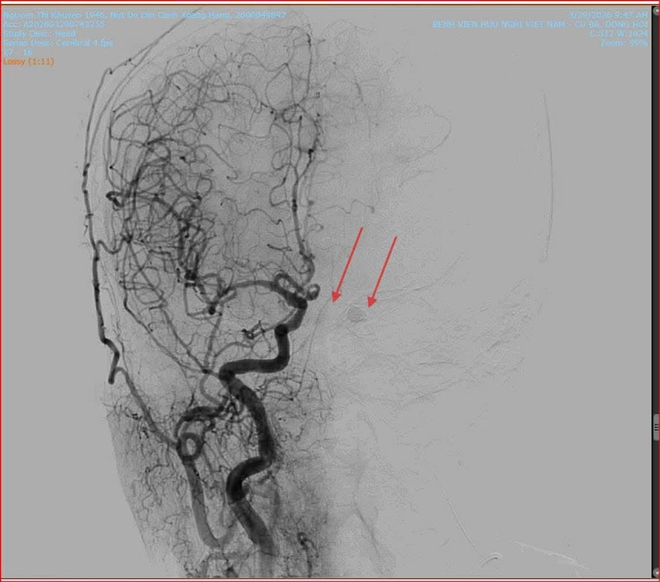

Khi thăm khám cho bệnh nhân, các bác sĩ Khoa Mắt phát hiện mắt trái của cụ K. giảm thị lực, tăng nhãn áp, lồi mắt, giãn tĩnh mạch thượng củng mạc, phù nề kết mạc, hạn chế vận nhãn. Nghi ngờ bệnh nhân bị rò động mạch cảnh xoang hang trái, các bác sĩ đã chỉ định chụp X- Quang số hóa xóa nền (DSA) và có kết quả rò động mạch cảnh xoang hang bên trái.

Nhận định đây là ca bệnh có diễn tiến phức tạp, nếu không điều trị kịp thời có thể dẫn đến mù lòa vĩnh viễn hoặc xuất huyết não, ê-kíp các bác sĩ can thiệp mạch của hai bệnh viện đã quyết định thực hiện phương pháp can thiệp nội mạch nút lỗ rò. Dưới sự hỗ trợ của hệ thống chụp mạch số hóa xóa nền (DSA), các bác sĩ đã khéo léo đưa ống thông (microcatheter) từ động mạch đùi lên vị trí tổn thương tại xoang hang.

Các bác sĩ đã can thiệp nút lỗ rò động mạch cảnh xoang hang dưới sự hỗ trợ của hệ thống chụp mạch số hóa xóa nền (DSA).

Tại đây, vật liệu can thiệp Coil và keo sinh học được đưa vào để bít kín lỗ rò một cách chính xác nhất, giúp tái lập lại dòng chảy bình thường cho mạch máu não. Ca can thiệp diễn ra thành công tốt đẹp.

Vị trí rò động mạch (ảnh trái) và sau khi can thiệp bít lỗ rò (ảnh phải).